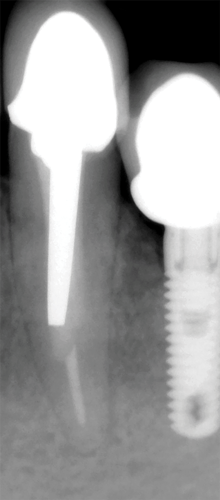

The traditional custom cast dowel core provides a better geometric adaptation to excessively flared or elliptical canals and almost always requires minimal removal of tooth structure.1 Custom cast posts and cores adapt well to extremely tapered canals or those with a noncircular cross section and/or irregular shape and roots with minimal remaining coronal tooth structure.22 Patterns for custom cast posts can be formed either directly in the mouth or indirectly in the laboratory. Regardless, this method requires two appointment visits and a laboratory fee. Also, because it is cast in an alloy with a modulus of elasticity that can be as high as 10 times greater than that of natural dentin,40 this possible incompatibility and rigidity can create stress concentrations in the less rigid root, resulting in post separation or failure.41,42 Additionally, the transmission of occlusal forces through the metal core can focus stresses at specific regions of the root, causing root fracture (Figure 3).40 Furthermore, upon esthetic consideration, the cast-metal post can result in discoloration and shadowing of the gingiva and the cervical aspect of the tooth (Figure 4).43

Fig 3. Occlusal forces were transmitted through the metal post in the mandibular right canine, and stress concentrations were focused in the mesial aspect of the apical one-third of the root, resulting in a horizontal fracture.

Figure 3